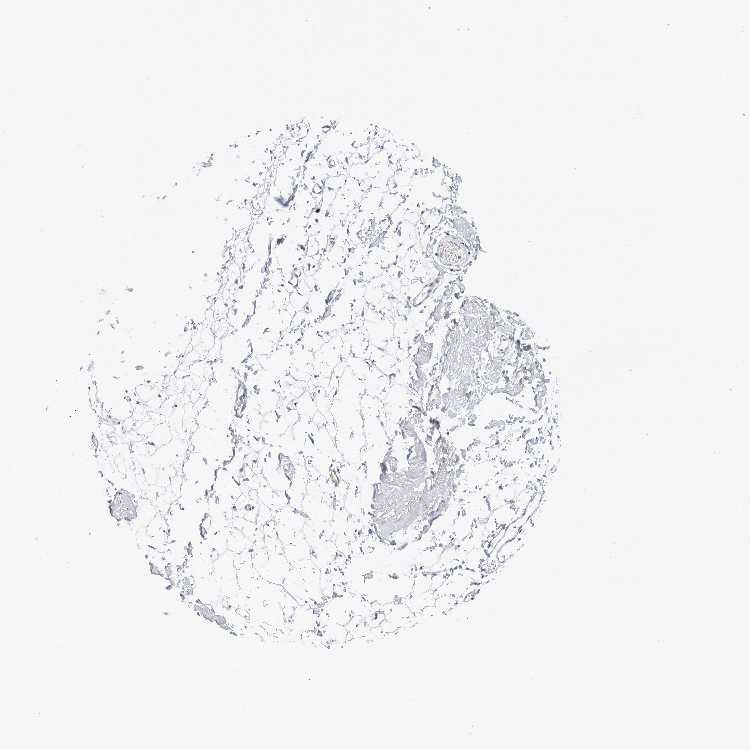

ADIPOSE TISSUE - Antibody stainingi

Antibody staining in the annotated cell types in the current human tissue is reported as not detected, low, medium, or high, based on conventional immunohistochemistry profiling in selected tissues. This score is based on the combination of the staining intensity and fraction of stained cells.

Each image is clickable and will lead to virtual microscopy that enables deeper exploration of all samples and also displays staining intensity scores, fraction scores and subcellular localization as well as patient and tissue information for each sample.

Antibody HPA027529Antibody HPA074638Antibody CAB033120

Adipocytes Not detectedMediumLow